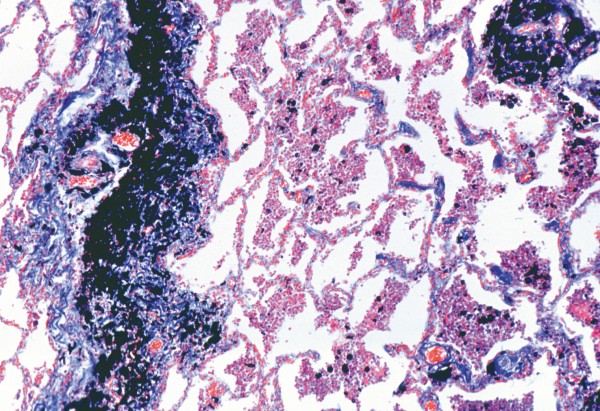

Kohlenstaublunge (Anthracosis pulmonum) des Menschen, quer.

Produktinformationen "Kohlenstaublunge (Anthracosis pulmonum) des Menschen, quer."

Gebiet: Krankheitserreger & erkrankte Organe